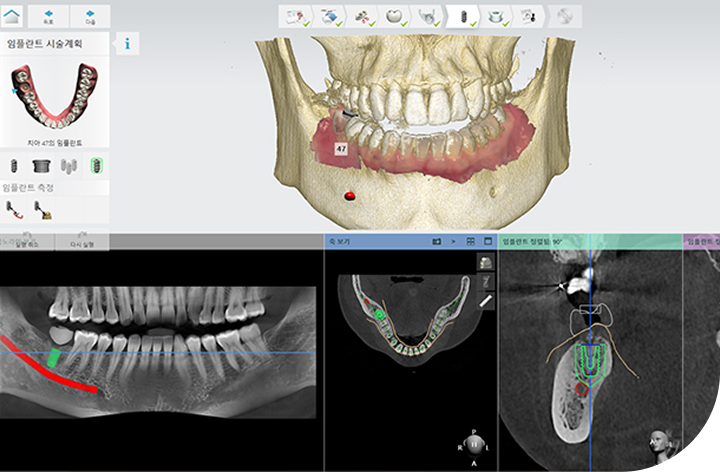

환자의 구강 정보를 디지털 데이터를 기반으로 3D 가상 모의 수술을

진행해 기존 방식 대비 수술 시간이 짧아 체력적 부담을 줄여주고

최소 절개로 통증 및 붓기 최소화로 면역력이 약하거나 회복력이 더딘

고령의 환자, 고혈압 당뇨 등 전신질환을 앓고 계신 분들도 부담없이 안전하게 수술받을 수 있습니다.